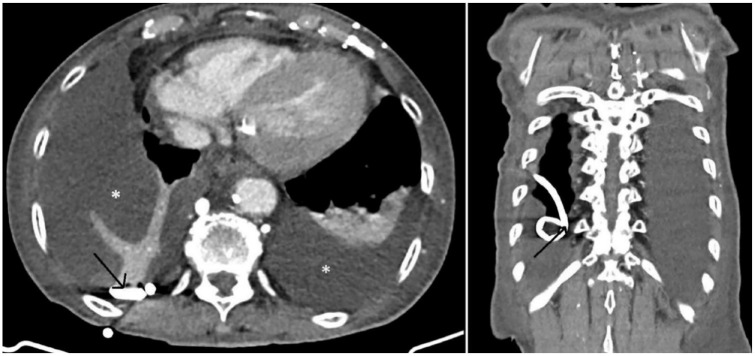

Case presentation: A 68-year-old female patient underwent PleurX tube insertion due to malignant pleural effusion. On the third week of insertion, she complained of itching and pain at the site of insertion, a grayish-white worm was visualized at the insertion site. Ascaris lumbricoides was identified by microbiological examination. She received 400 mg of albendazole.